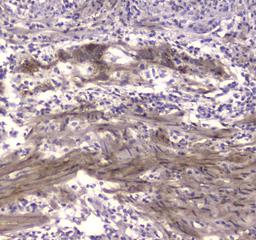

Boster Bio Anti-Creatine kinase B type/CKB Antibody Picoband™ catalog # A01695-1. Tested in ELISA, IHC, WB applications. This antibody reacts with Human, Mouse, Rat.